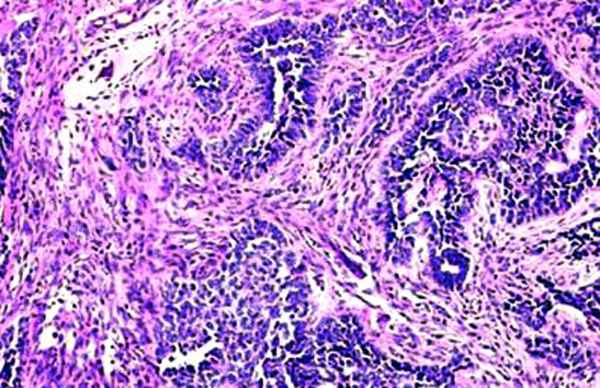

Yesterday our pathologist presented a preliminary conclusion - lytic GCT. Will pass specimens to colleagues from other facilities.

I spent my early orthopaedic surgical experience at an Italian bone tumor center. I have seen many GCTs of the bone, but none is similar to that you presented. I hope that this is a my error, but

it, in my opinion, appears aggressive and strange in diaphyseal localization. It seems in some aspects similar to a teleangectatic osteosarcoma, a variant of osteosarcoma (characteristic gross appearance of telangiectatic osteosarcoma is a multi-cystic "bag of blood". Microscopically, telangiectatic osteosarcoma has large blood filled spaces and thin septation. Within the septa there is scanty osteoid production by the pleomorphic malignant cells. Giant cells are not rare)

"Microscopic features (of teleangiectatic osteosarcoma):

Malignant cells are noted in a background of blood and necrotic debris. Because the pleomorphic hyperchromatic malignant cells may be diluted in the necrotic and hemorrhagic background, a careful examination to recognize these elements is imperative. Blood lakes, rather than endothelium-lined spaces, are present. In some cases, an osteoid matrix may not be visualized except within the septal walls, which may be thin and difficult to find. In such cases, a characteristic radiographic appearance, when correlated with a careful microscopic search for features suggestive of malignancy, helps in the correct interpretation of the findings.25 In some cases, low-power examination reveals a morphologic pattern that is reminiscent of an aneurysmal bone cyst (see Image 1).

A potential trap is created by a radiologic impression of an aneurysmal bone cyst and the characteristic gross features of that cyst. However, examination of the cyst lining reveals overt malignant cells, often with increased mitotic activity (see Image 2). These cells may lie adjacent to the benign osteoclastic giant cells. In some cases, these giant cells are numerous, and the tumor mimics a giant, cell-rich osteosarcoma (see Image 3). Unlike an aneurysmal bone cyst, telangiectatic osteosarcoma has an osteoid matrix that is delicate and lacelike in appearance. Also, the stroma between the dilated vascular spaces often contains malignant cells."

I agree with you about possibility of the teleangioasaroma in this case, but why did morphologysts not see pathological mytosis and cell atypia? More over there is no huge negative X-ray dynamic changes from november 2007, patient had no pain, tenderness, skin changes and other malignant tumors signs. Becouse of that there is a little doubt for malignant nature of this lesion.

Пока наш морфолог подтверждает гигантоклеточную опухоль, литическую форму. Препараты передали еще и в другие учреждения, пока информации оттуда нет.